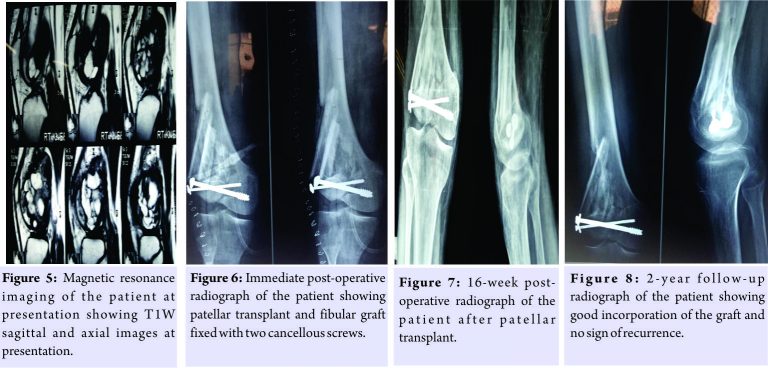

Complete surgical excision of the tumor and articular surface reconstruction was planned as described by D’ Aubigne [4]. A 15-cm long vertical incision was made over anterolateral aspect of distal thigh and right knee and quadriceps tendon, patella and patellar tendon exposed. A 3-cm wide, musculovascular pedicle separated at inferior border of vastus lateralis muscle, approximately 10-cm proximal from lateral border of patella. Patella was then enucleated from rest of its attachments, releasing quadriceps tendon all around except the pedicle, leaving a rim of 4-mm soft tissue to spare vascular supply. Lateral condyle of femur was exposed and excised en bloc with whole tumor mass with the help of saw and osteotome. The deep articular surface and medial aspect of patella were freshened. The anterior surface which was to be used as articular surface was rotated inferiorly, brought at the level of medial condyle and the patella was fixed with two lag screws as depicted in Fig. 6. The rest of the condylar defect was filled with fibular strut graft and bone chips from iliac crest. The extensor mechanism repair was done by turning down the aponeurotic flap of rectus femoris and suturing it to patellar tendon and vastus expansion. Wound closure done after hemostasis achieved. Bulky dressings with a long posterior plaster of Paris (POP) slab applied which were changed on the 2nd post-operative day. Knee was kept in posterior POP slab for immobilization up to 6 weeks and active mobilization exercises started subsequently. Patient was kept non-weight-bearing till adequate radiological strength achieved, i.e., 16 weeks (Fig. 7) and a knee brace was worn while walking with a stick support up to 1 year. Patient recovered uneventfully and at the end of 2 years there was no sign of recurrence or deformity with good function as he walks without support and performs his routine activities with fair range of movements (0–80°). Radiological evaluation suggested good healing of lesion without any evidence of osteolysis or collapse of reconstructed lateral femoral condyle (Fig. 8). The quadriceps strength was found to be of Grade 4/5. There was no laxity or instability. Musculoskeletal tumor society score [7] was found to be 25 suggesting gratifying outcome. The patient is to be followed up for the long-term results.